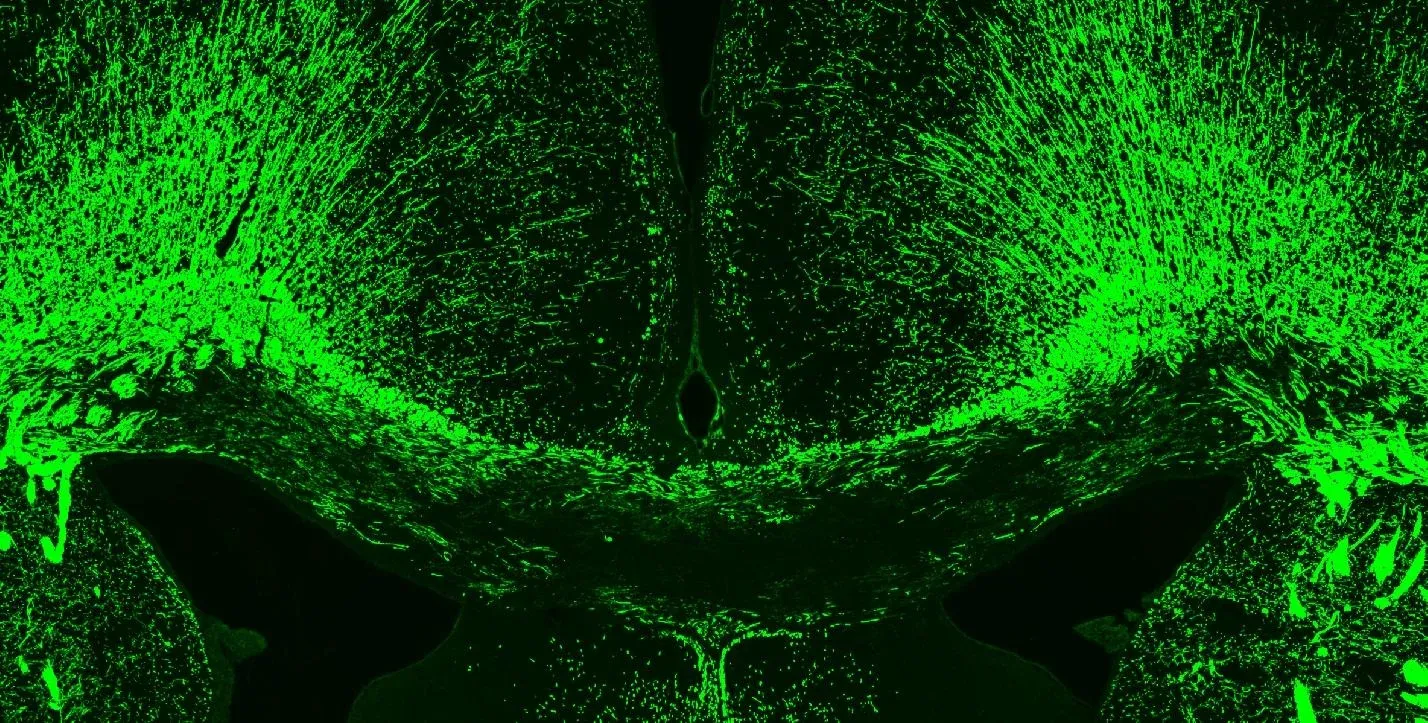

Neuroinflammation (microglia & astrocytes) in the corpus callosum of the cuprizone mouse model.

Activated Microglia & Reactive Astrocytes

Neuroinflammation is a key pathological feature of MS with activated microglia and reactive astrocytes playing key roles in pathogenesis. In our EAE models, microglia & astrocytes are abundant in the spinal cord. In the cuprizone model, neuroinflammation is prominent during the demyelination phase of the disease and resolves as remyelination occurs.